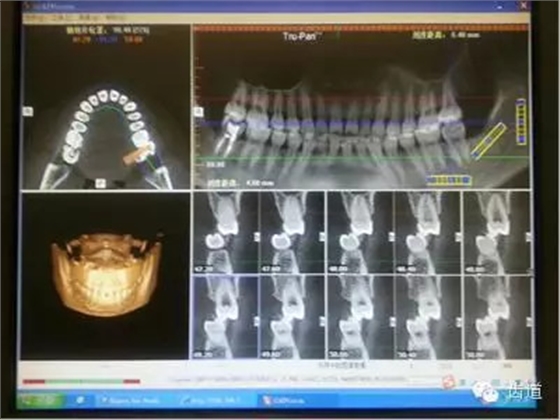

來源:齒道 源于“齒道-(牙合)學(xué)學(xué)習(xí)群”病案討論 文字編輯整理:周文翹 微信編輯:黃春梅 總編: 齒道—(牙合)學(xué)微信群里大咖云集,是廣大(牙合)學(xué)愛好者的相互學(xué)習(xí)、共同討論的理想平臺。(牙合)學(xué)并不神秘,群(牙合)學(xué)老師權(quán)花淑認(rèn)為:每一位臨床醫(yī)生每天都會面臨各種困惑和難題,作為初學(xué)者,只要我們堅持思考、善于溝通、勤于實(shí)踐,(牙合)學(xué)的神秘大門將會為我們敞開。下面,讓我們跟隨近日學(xué)習(xí)群里的部分病例,尋找(牙合)學(xué)的蛛絲馬跡。 圖1 權(quán)老師從(牙合)學(xué)的角度提出: 以上側(cè)片中應(yīng)關(guān)注舌的位置,由此會引發(fā)出更多需要關(guān)注的問題(如:舌的位置是否與氣道、牙弓狹窄、中線偏斜等有關(guān))。 病例二:(權(quán)老師會診病例圖2、圖3)患者,女,24歲。主訴:左側(cè)顳下頜關(guān)節(jié)區(qū)張口疼痛,打哈欠時疼痛更明顯。從以下CBCT截圖中,我們能讀出哪些信息? 圖2 圖3 多位醫(yī)生均發(fā)現(xiàn): 左7正鎖合,47根管治療,中線不齊,切端對刃,下前牙扭,下前牙牙根吸收等問題。同時也提出一些疑問:前伸(牙合)是否有異常,髁突是否對稱,關(guān)節(jié)盤的位置是否正常等。 權(quán)老師指出: 通過CT和臨床檢查,患者覆蓋和覆(牙合)不足;開口度尚可,開口型呈“Z”型軌跡;左側(cè)咬肌區(qū)有輕微壓痛,無明顯彈響和其他雜音;髁突疑似吸收,升支似乎變短。初步診斷正鎖合是引起同側(cè)TMJ疼痛的原因。雖然信息有限,但我們依然可以從中學(xué)習(xí)到東西,用(牙合)學(xué)的思維去驗證和排除我們的疑問和猜想。 權(quán)老師從(牙合)學(xué)的角度提出: 磨耗是一種慢性疾病,任何時候都是亡羊補(bǔ)牢。后牙單顆牙磨耗的情況是不存在的,只是個別牙會表現(xiàn)得更明顯。要從整個牙列甚至整個口頜系統(tǒng)去分析,還應(yīng)該權(quán)衡整體解決或保守治療。單顆牙修復(fù)可視為一種方法,但它是保守被動的治療方法。 以上病例,你是否用(牙合)學(xué)的眼光捕捉到一些蛛絲馬跡了?請繼續(xù)跟隨權(quán)老師學(xué)習(xí),讓我們一起漸入佳境! 貼心的權(quán)老師推薦(牙合)學(xué)初學(xué)者們把(牙合)學(xué)教材作為入門書,同時推薦了王美清老師、韓科老師、謝秋菲老師編寫的有關(guān)書籍。 合學(xué)的世界邀請您 中國醫(yī)學(xué)界,牙醫(yī)是個非常特別的群體! 自由執(zhí)業(yè)度最高的,是牙醫(yī)! 最有活力的,也是牙醫(yī)! 最愛學(xué)習(xí)的,還是牙醫(yī)! 每次研修,都好象畫圓。學(xué)得越多,圓的半徑越大。圓畫得越大,接觸的東西也越多…… 當(dāng)牙醫(yī)遇到合學(xué)時,一扇奇特的門打開了! 合學(xué),研究的是整個口頜系統(tǒng)的形態(tài)與功能,生理與病理,它不是玄學(xué),卻非常美妙。 學(xué)習(xí)合學(xué)開啟合學(xué)之門 優(yōu)秀牙醫(yī)必然的選擇